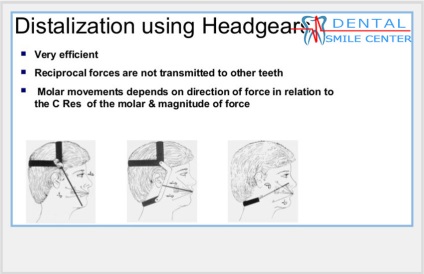

Vannak különböző lehetőségek distalization az őrlőfogak, de az egyik leghatékonyabb megoldásnak - az, hogy egy fej tolóerő. Rögzítőgyűrűk folyik hat foga. Mivel a gyűrű két cső, fel tudjuk használni azokat más célra. Ha azt szeretnénk, hogy alakulat mozgás, akkor használja a cső, amely közelebb áll a központban az ellenállás a fogat. Ha kell kezelni tipilnye mozgás azt jelenti, használt cső, ami távolabb van a központtól az ellenállás. A fej tolóerő alkalmazott a fejlődő szervezetben.